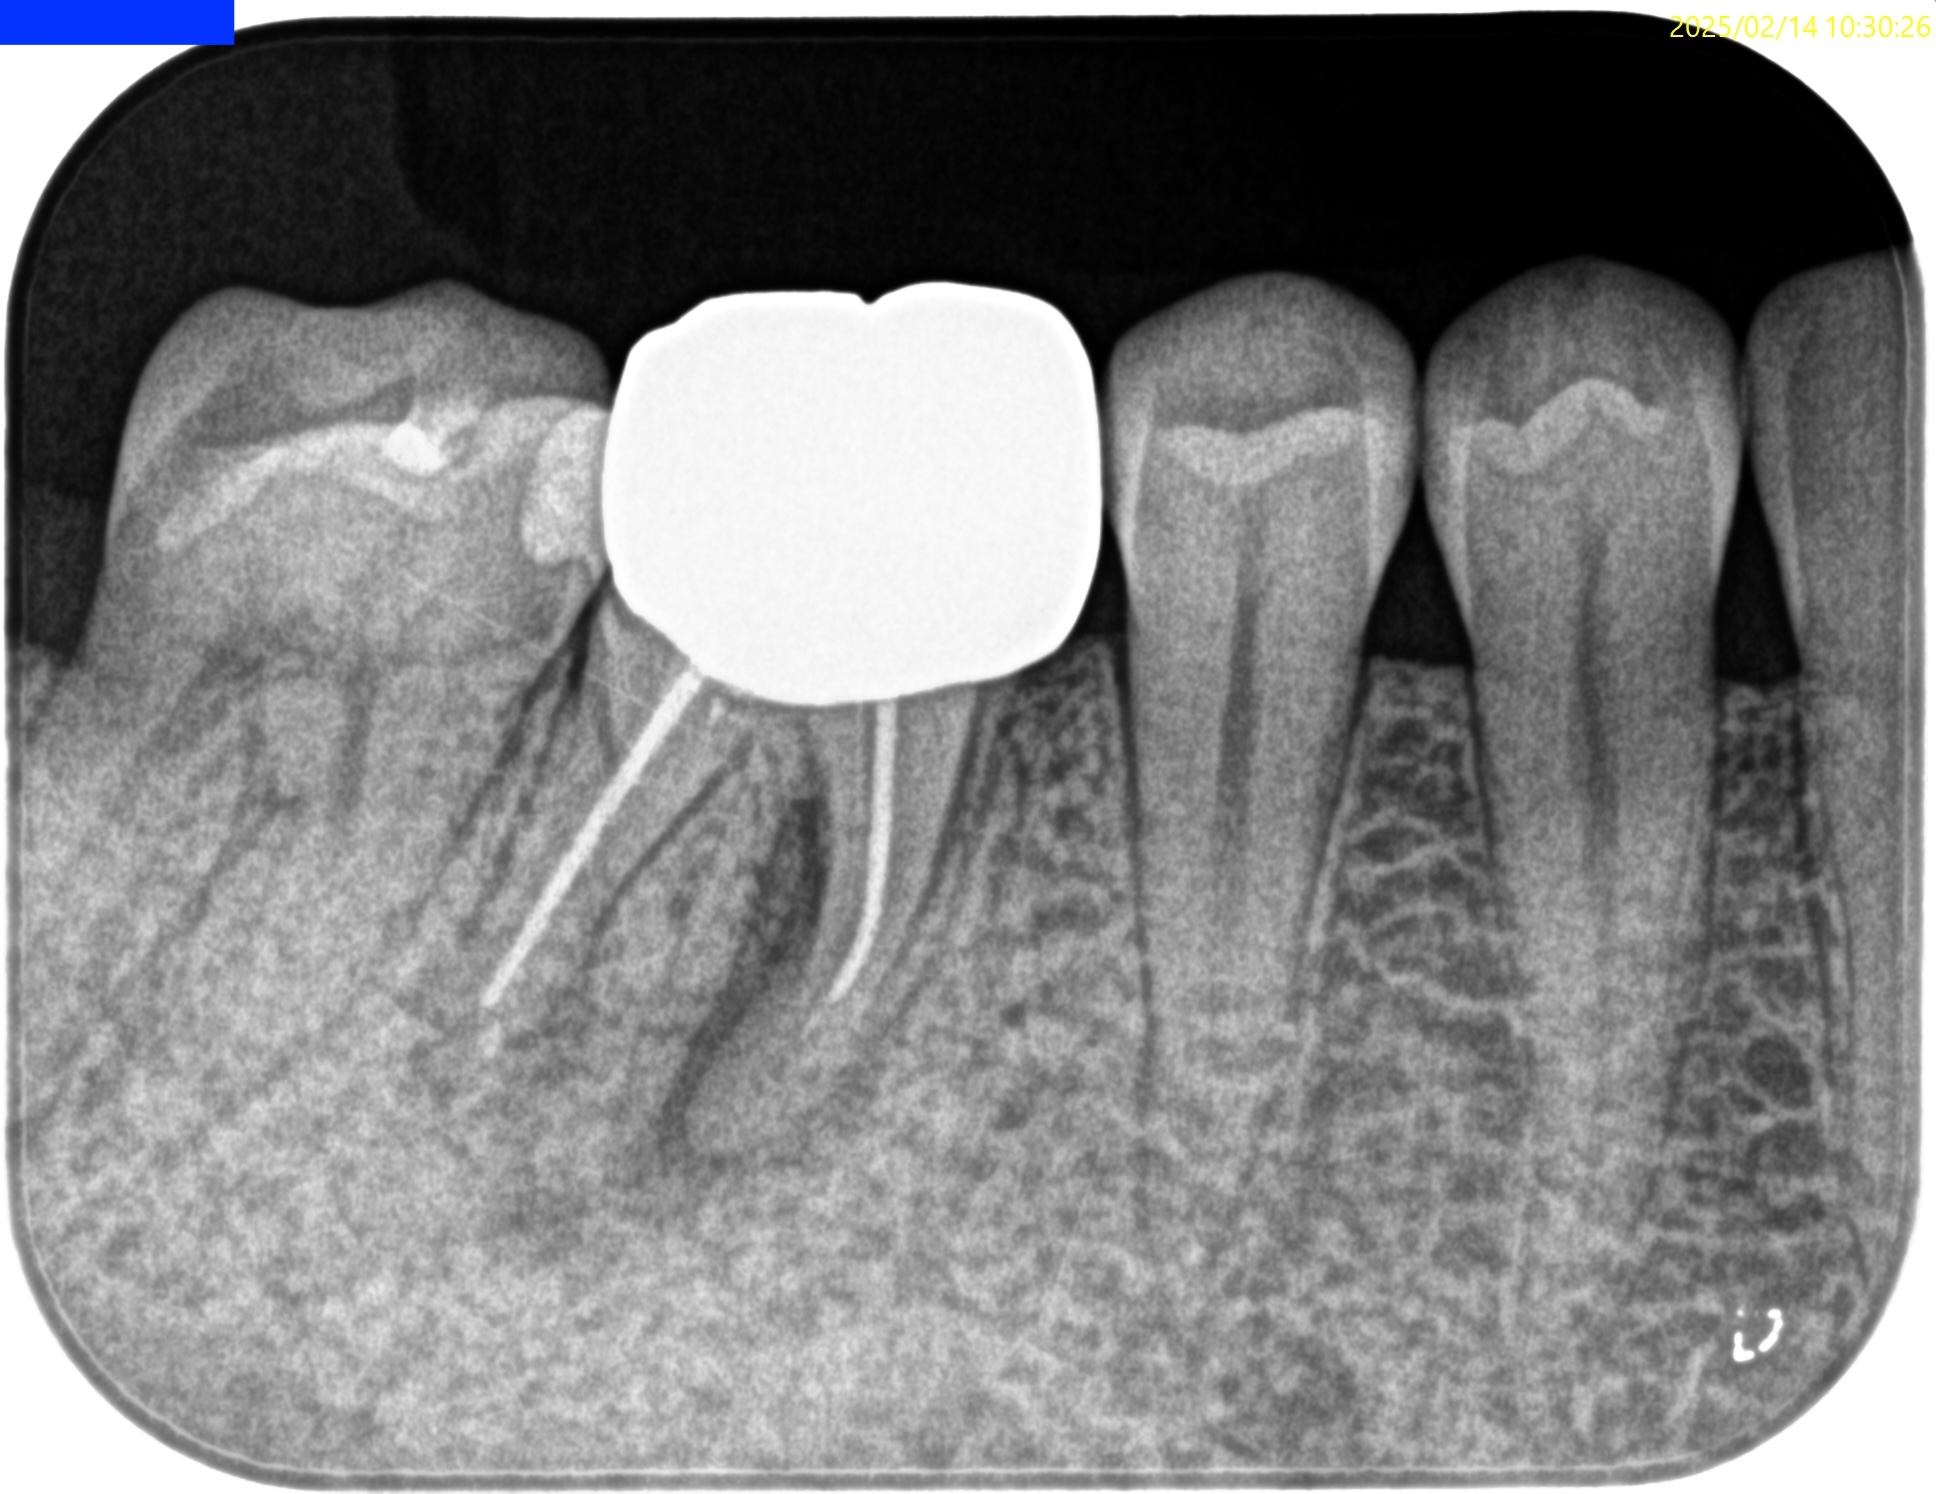

Pre-op Endo test(2025.2.14)

MB

ML

D

Radix

そこそこ湾曲度合いが強いRadix Entomolarisを有する#30だ。

が、D以外の根管はほぼ適切な根管治療がなされていない。

Radixにおいては未着手だ。

支台築造後にPA, CBCTを撮影した。

問題はないだろう。